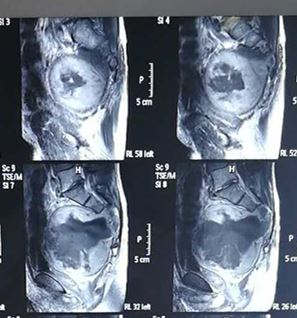

日前,我院关节与骨肿瘤外科与介入科、麻醉科、输血科、手术室等相关兄弟科室共同协作,顺利完成了一例全省较为罕见且手术难度极大的巨大骶骨肿瘤切除术。患者男性,52岁,因“大便变细1年余”入院,就诊于我院关节与骨肿瘤外科。据骶尾椎MRI检查显示,骶椎占位伴组织突入盆腔,考虑为脊索瘤可能,需要手术治疗。 但是,针对巨大的骶骨肿瘤,手术困难重重。首先,肿瘤瘤位于骶椎并突入盆腔,手术解剖难度大,且瘤体血供丰富,术中最关键的就是避免大出血;其次,要降低神经受压迫的症状,以保证患者术后正常行走及正常大小便功能;再次,肿瘤与骨盆及邻近脏器关系紧密,切除过程中需特别注意肿瘤对膀胱、直肠、腹部大血管等的压迫或侵犯。此外,腰骶部为躯体生物力学中枢,术后需要重建,且重建难度很大;最后,肿块巨大,切除后皮肤的缝合和愈合问题,术后的监护和治疗问题等,都是关系着预后的要点。

经过充分的术前准备,手术正式开始。在麻醉科的支持下,介入科熊壮主任在患者腹主动脉放置球囊,以防术中大出血。由关节与骨肿瘤外科胡勇主任主刀,在胡博医师等的配合下,后路完整切除直径约15cm的骶骨巨大肿瘤,并进行腰骶部重建。术后患者生命体征平稳,双下肢运动感觉正常,并能保留70%大小便功能。